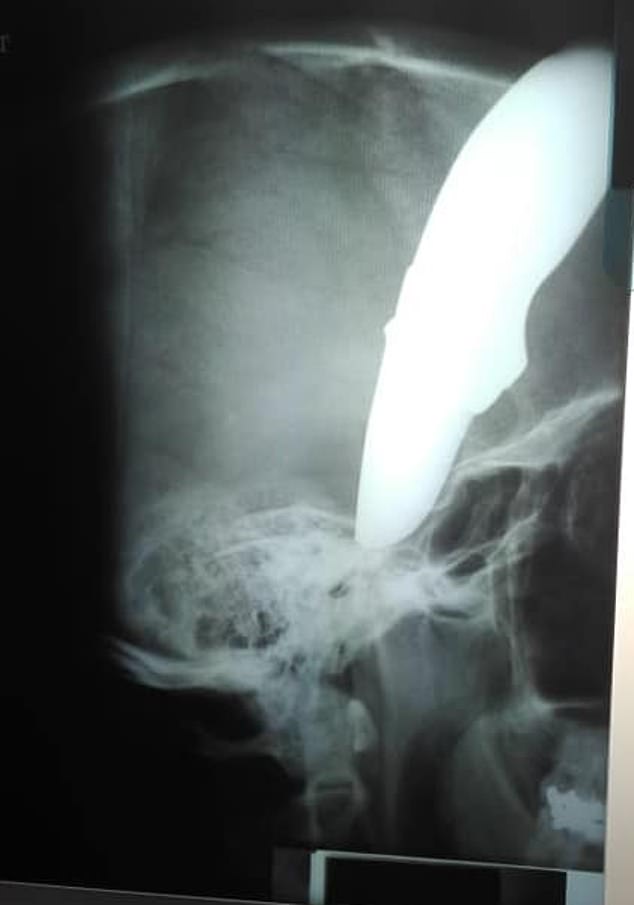

Ảnh chụp X-quang tình trạng của Shaun Wayne khi bị con dao găm vào đầu. |

“Bệnh nhân rất may mắn vì con dao đâm không đúng chỗ để có thể gây chết người. Hộp sọ khiến con dao bị cong và hướng ra bên ngoài”.